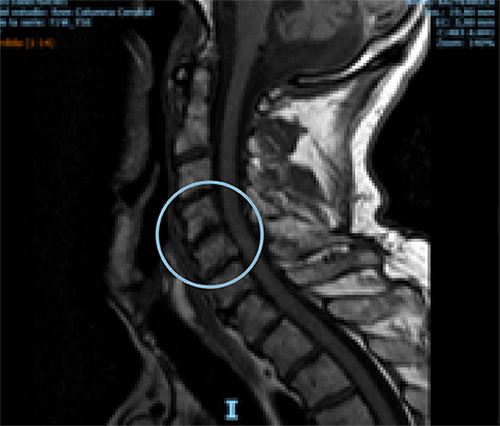

Comparative MRI of cervical spine pre- and one-year post-treatment in a 70-year-old man diagnosed with osteoarthritis of the cervical spine. The red arrow shows the remodeling of the affected disc.

PRE-TREATMENT

POST-TREATMENT